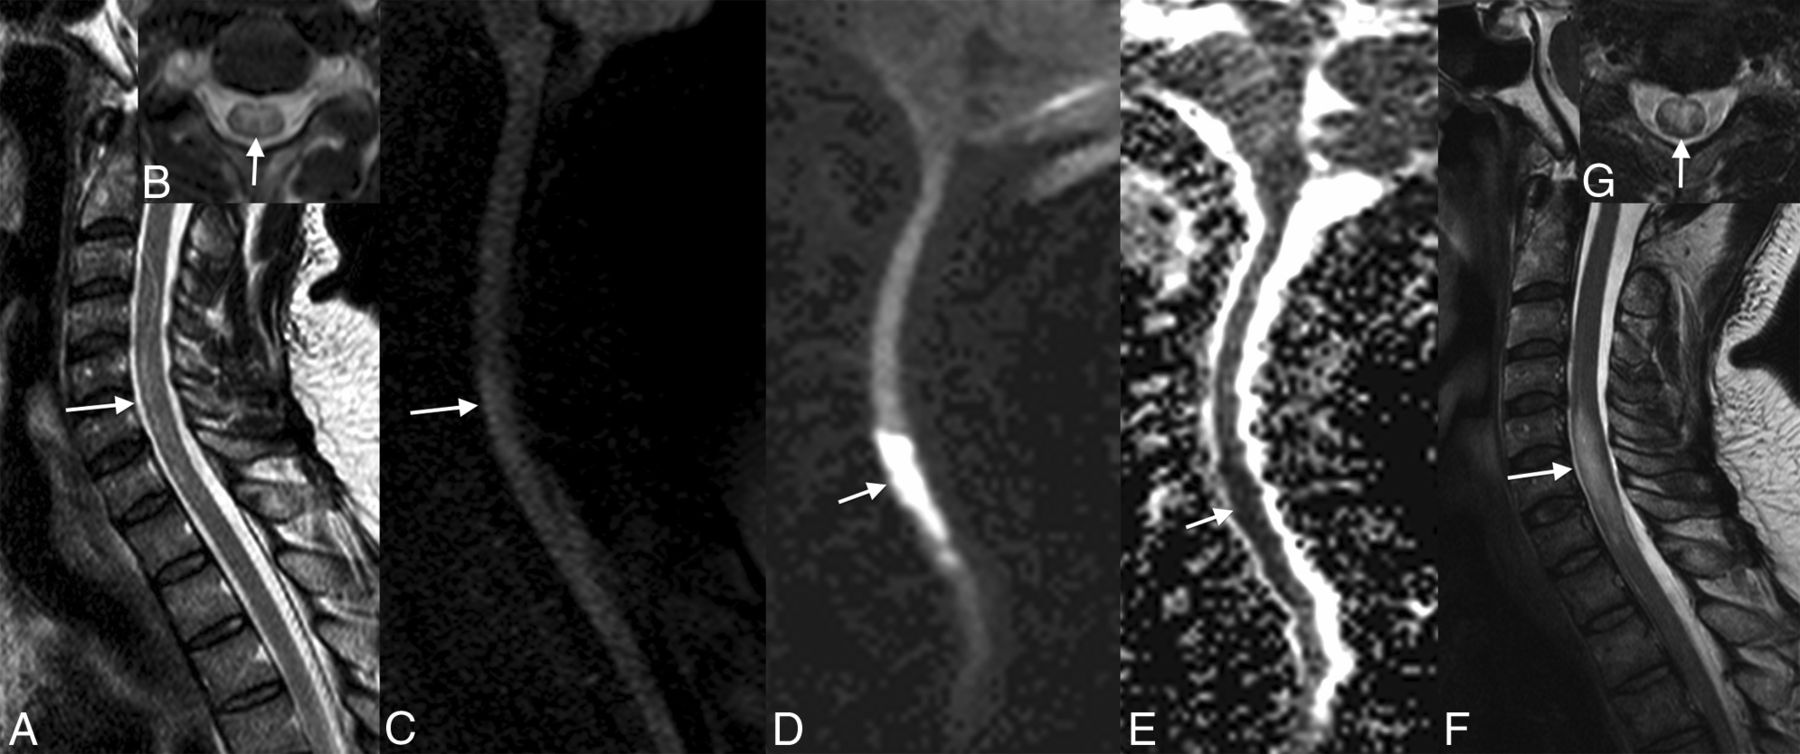

Evolution of ischemia. The first MR image shows the subtle signal anomaly on T2 and diffusion sequences (arrows, A–C). Follow-up 48 hours later shows an important tumefaction and high signal on T2WI associated with a restriction of diffusion of the cervical spinal cord at the C4–C7 levels (arrows, D–G).

In the acute stage, ischemia presents as a restriction in diffusion-weighted imaging of the spinal cord, hyperintense signal on T2 and STIR, and isointense on T1 and may be associated with a slight enlargement of the cord, without enhancement, which appears in the subacute phase (Figs 3 and 6).